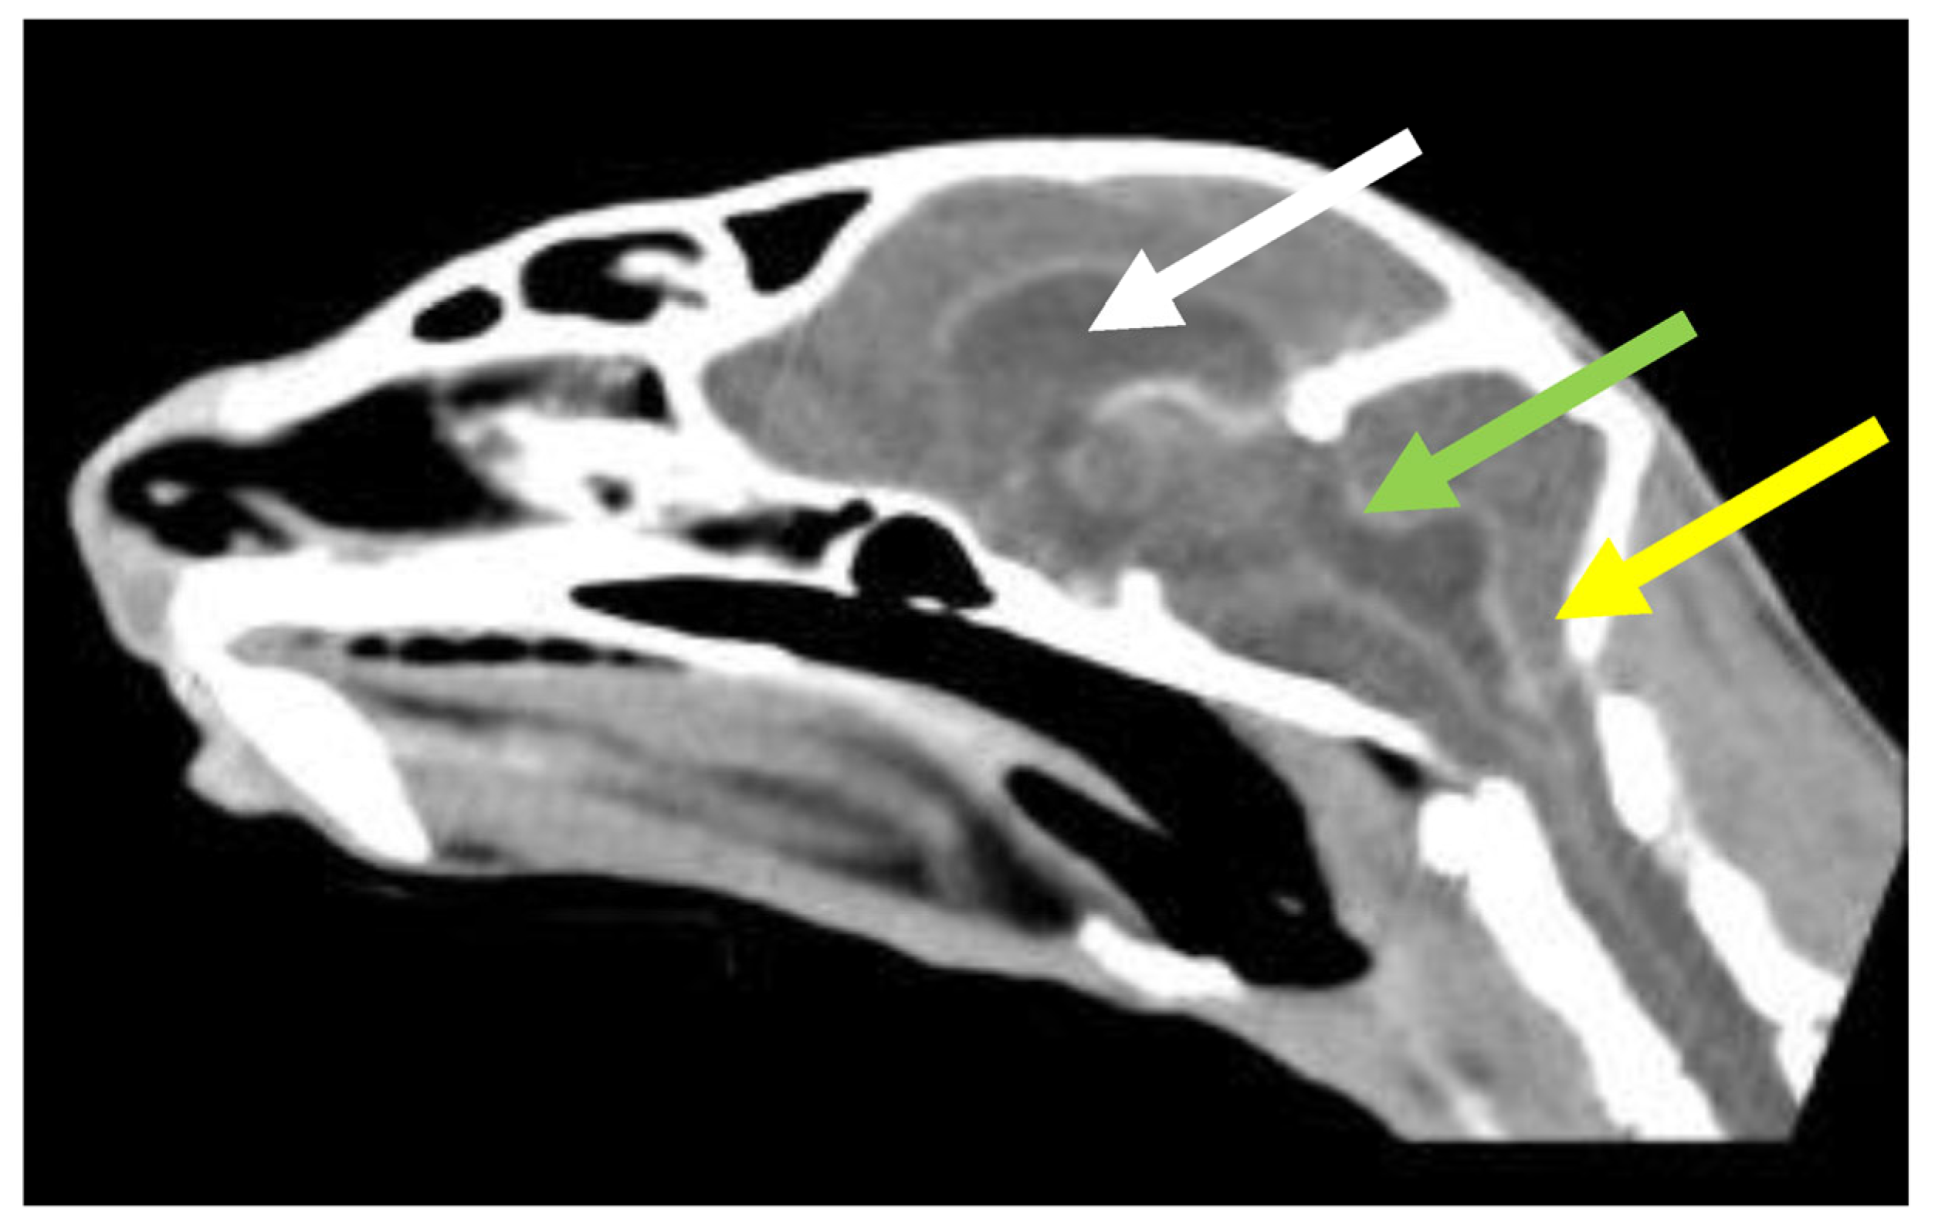

7.4. Diagnostic Imaging in FIP

7.4.2. Advanced Imaging of the CNS: MRI and CT

| Summary of Section 7: Diagnosis of FIP; Section 7.4: Diagnostic imaging in FIP: No specific ultrasonographic or radiographic findings exist for FIP. Ultrasonography (in particular) and radiography can show the presence of effusions. Pneumonia due to FIP that is occasionally reported can be associated with radiographic changes. Ultrasonography can reveal abdominal lymphadenomegaly or lymphadenopathy and/or abnormalities of the liver, spleen, intestines and/or kidneys (which can include a medullary rim sign), depending on which organs are affected. Imaging can also be of use to the direct sampling of abnormal tissues, e.g., fine-needle aspirate for cytology examination to reveal non-septic pyogranulomatous inflammation, or ultrasound-guided needle core (e.g., tru-cut) biopsies can be collected and submitted for histopathology. When a cat is showing neurological signs, the imaging of the brain by magnetic resonance imaging, if available, with contrast, can be useful to demonstrate neurological abnormalities (such as obstructive hydrocephalus, syringomyelia, foramen magnum herniation and marked contrast enhancement of the meninges, third ventricle, mesencephalic aqueduct, and brainstem). A description of computerised tomography findings in cats with neurological FIP has not been published, but MRI is likely to be more sensitive in the detection of subtle intraparenchymal lesions. Advanced imaging of the central nervous system is indicated before performing cerebrospinal fluid sampling to assess the potential risk of herniation. |